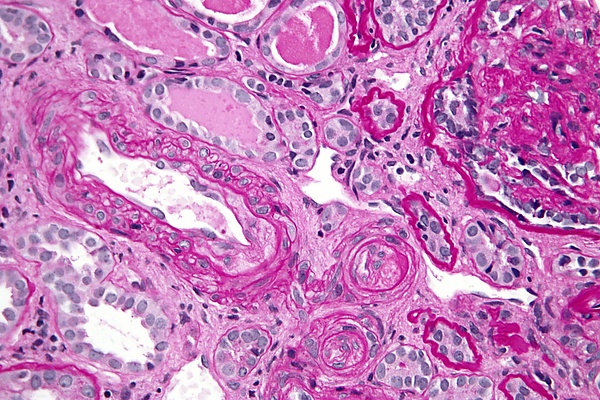

Наличие антифосфолипидных антител в отсутствие тромбов или связанных с беременностью осложнений не указывает на АФС. Антифосфолипидный синдром может привести к образованию артериальных или венозных сгустков крови в любых органах, или к связанным с беременностью осложнениям[6] . У пациентов с АФС наиболее распространённым симптомом является тромбоз глубоких вен нижних конечностей, а также артериальный тромбоз. У беременных женщин, страдающих АФС, существует повышенный риск выкидыша, внутриутробного ограничения роста плода и преждевременных родов. Часто причиной таких осложнений является плацентарный инфаркт.

Антифосфолипидный синдром может быть первичным или вторичным, обе формы имеют одинаковые проявления — тромбозы с локализацией в артериях или в венах. Антифосфолипидные антитела способны нарушить имплантационный процесс и свойства эмбриональных клеточных структур, что приводит к запуску патологических процессов — развитию тяжёлых воспалительных заболеваний и гибели клеток[13].